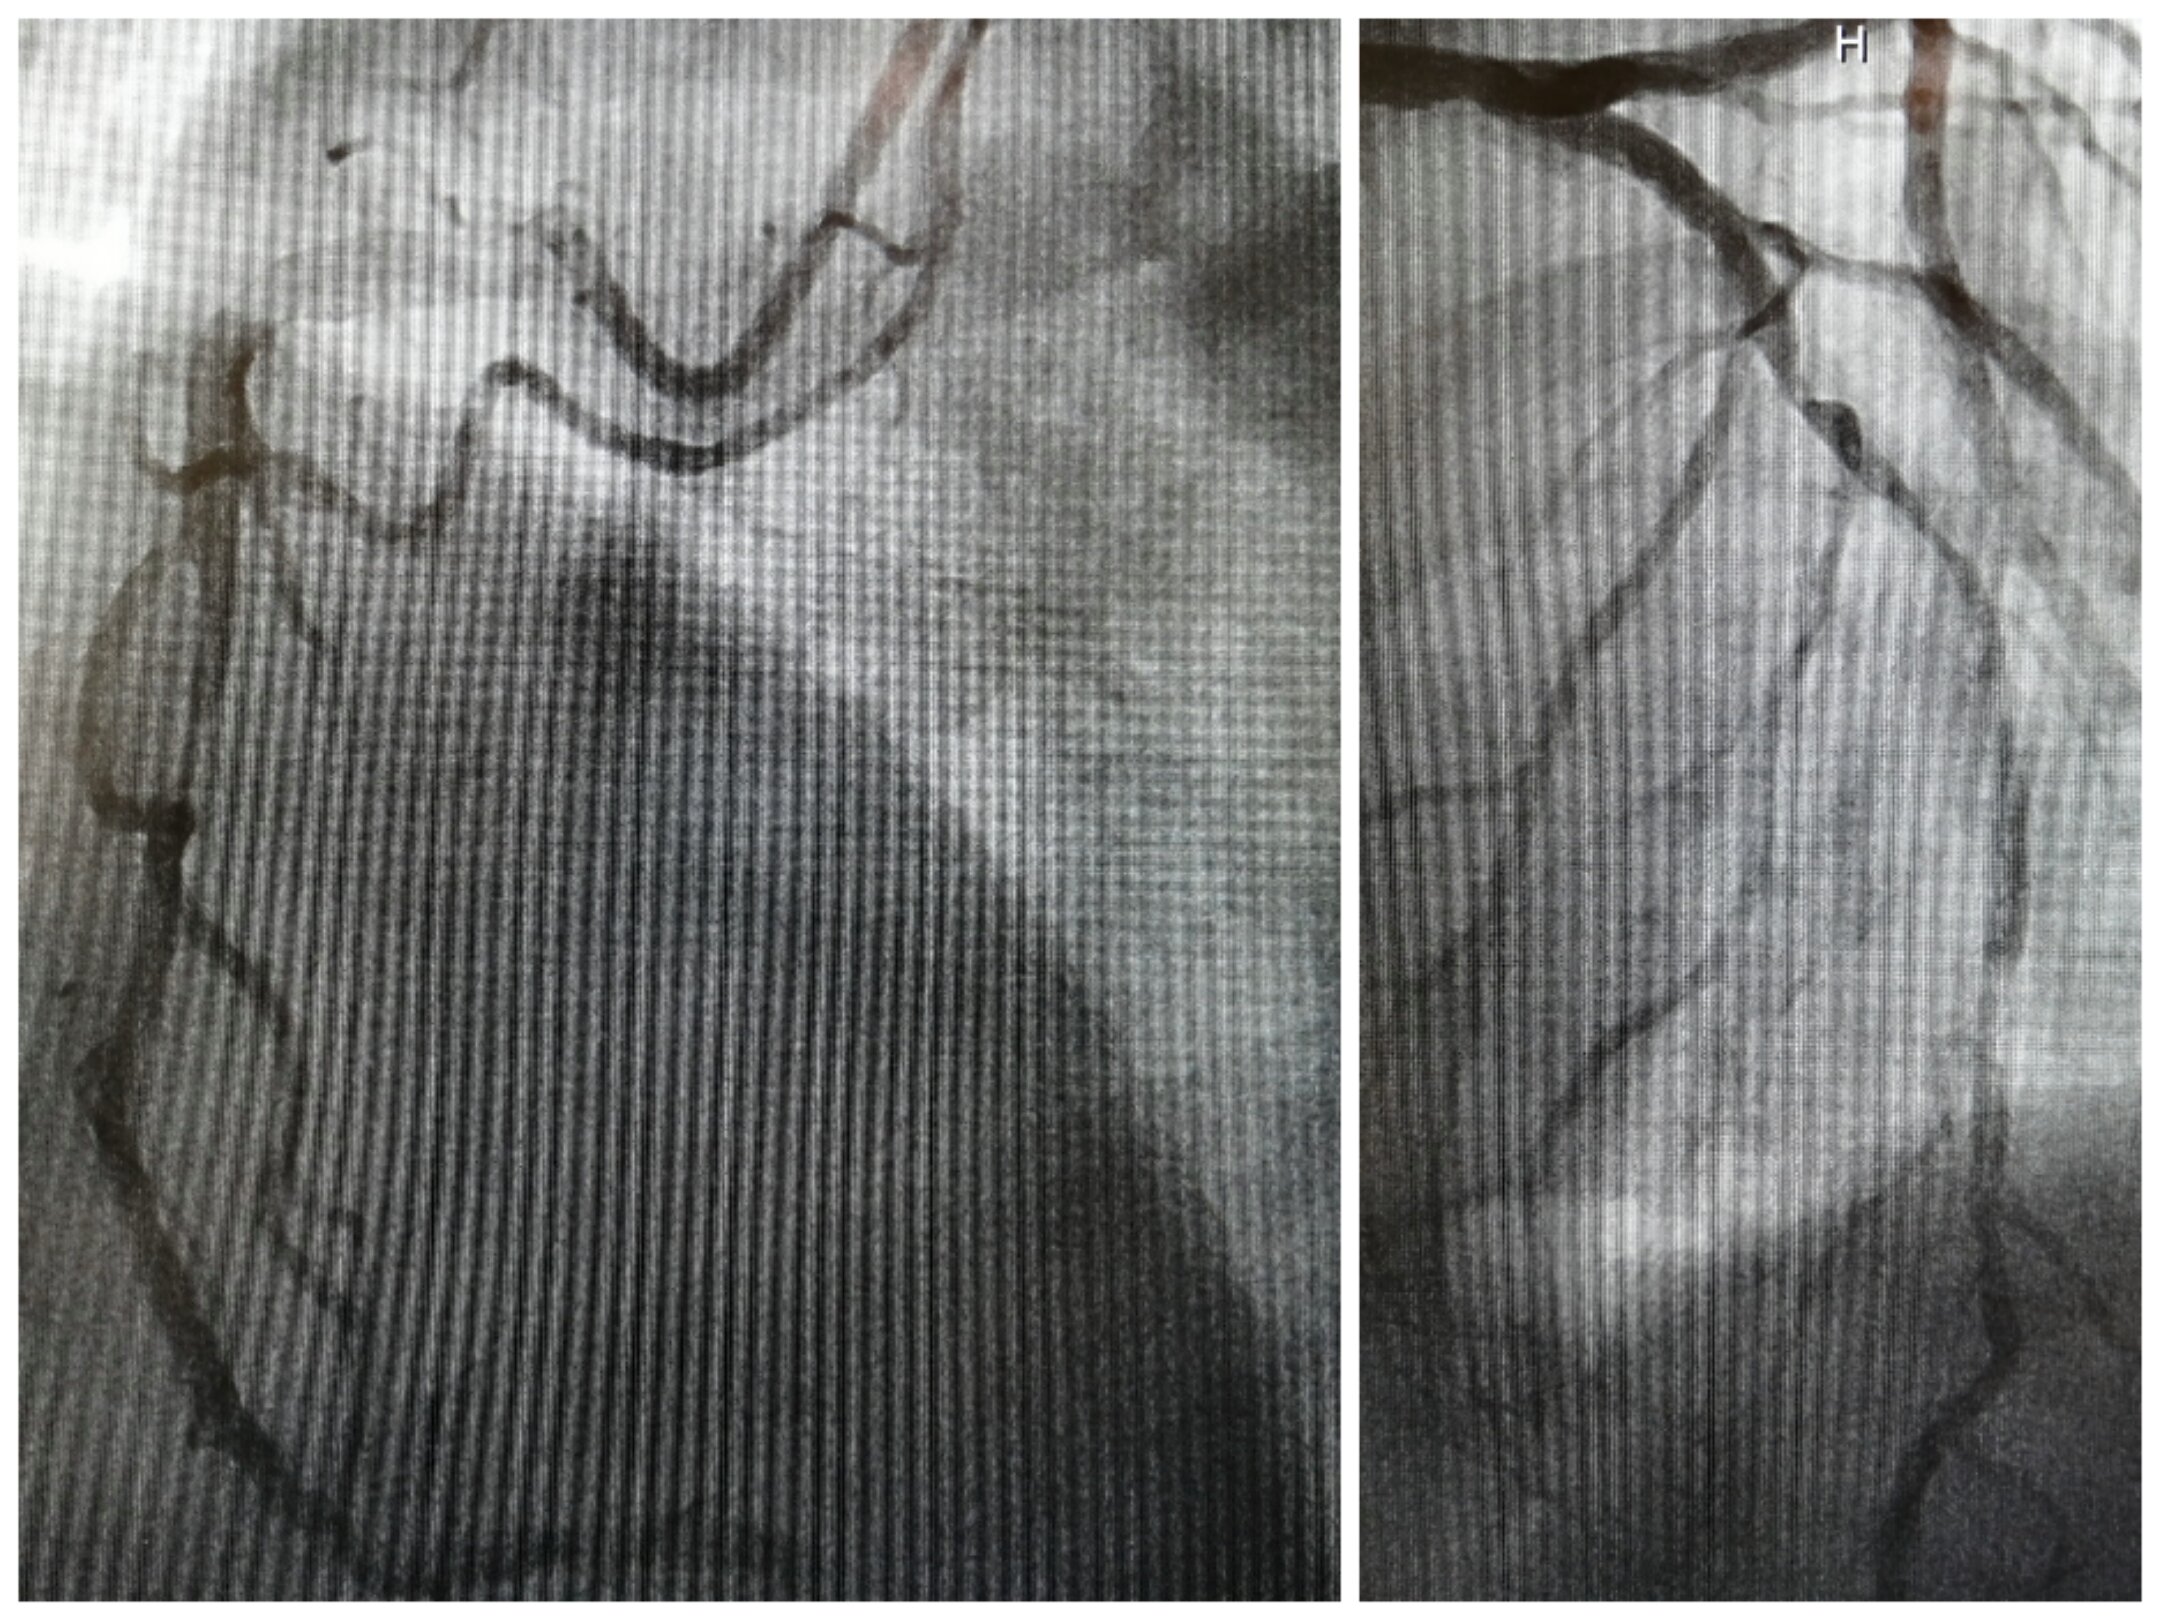

為了進(jìn)一步明確導(dǎo)致患者心衰的“元兇”,使患者得到更為精準(zhǔn)的治療,李慧新主任及楊光醫(yī)生為患者完善了冠脈造影檢查。造影提示:冠脈三支病變(右冠近中段99%狹窄,前降支中段85%狹窄,回旋支遠(yuǎn)段60%狹窄),予以右冠狀動(dòng)脈行支架植入治療。術(shù)后,患者心衰癥狀明顯緩解,胸悶氣喘的癥狀沒(méi)有再出現(xiàn),她和家人均對(duì)治療結(jié)果表示滿意。